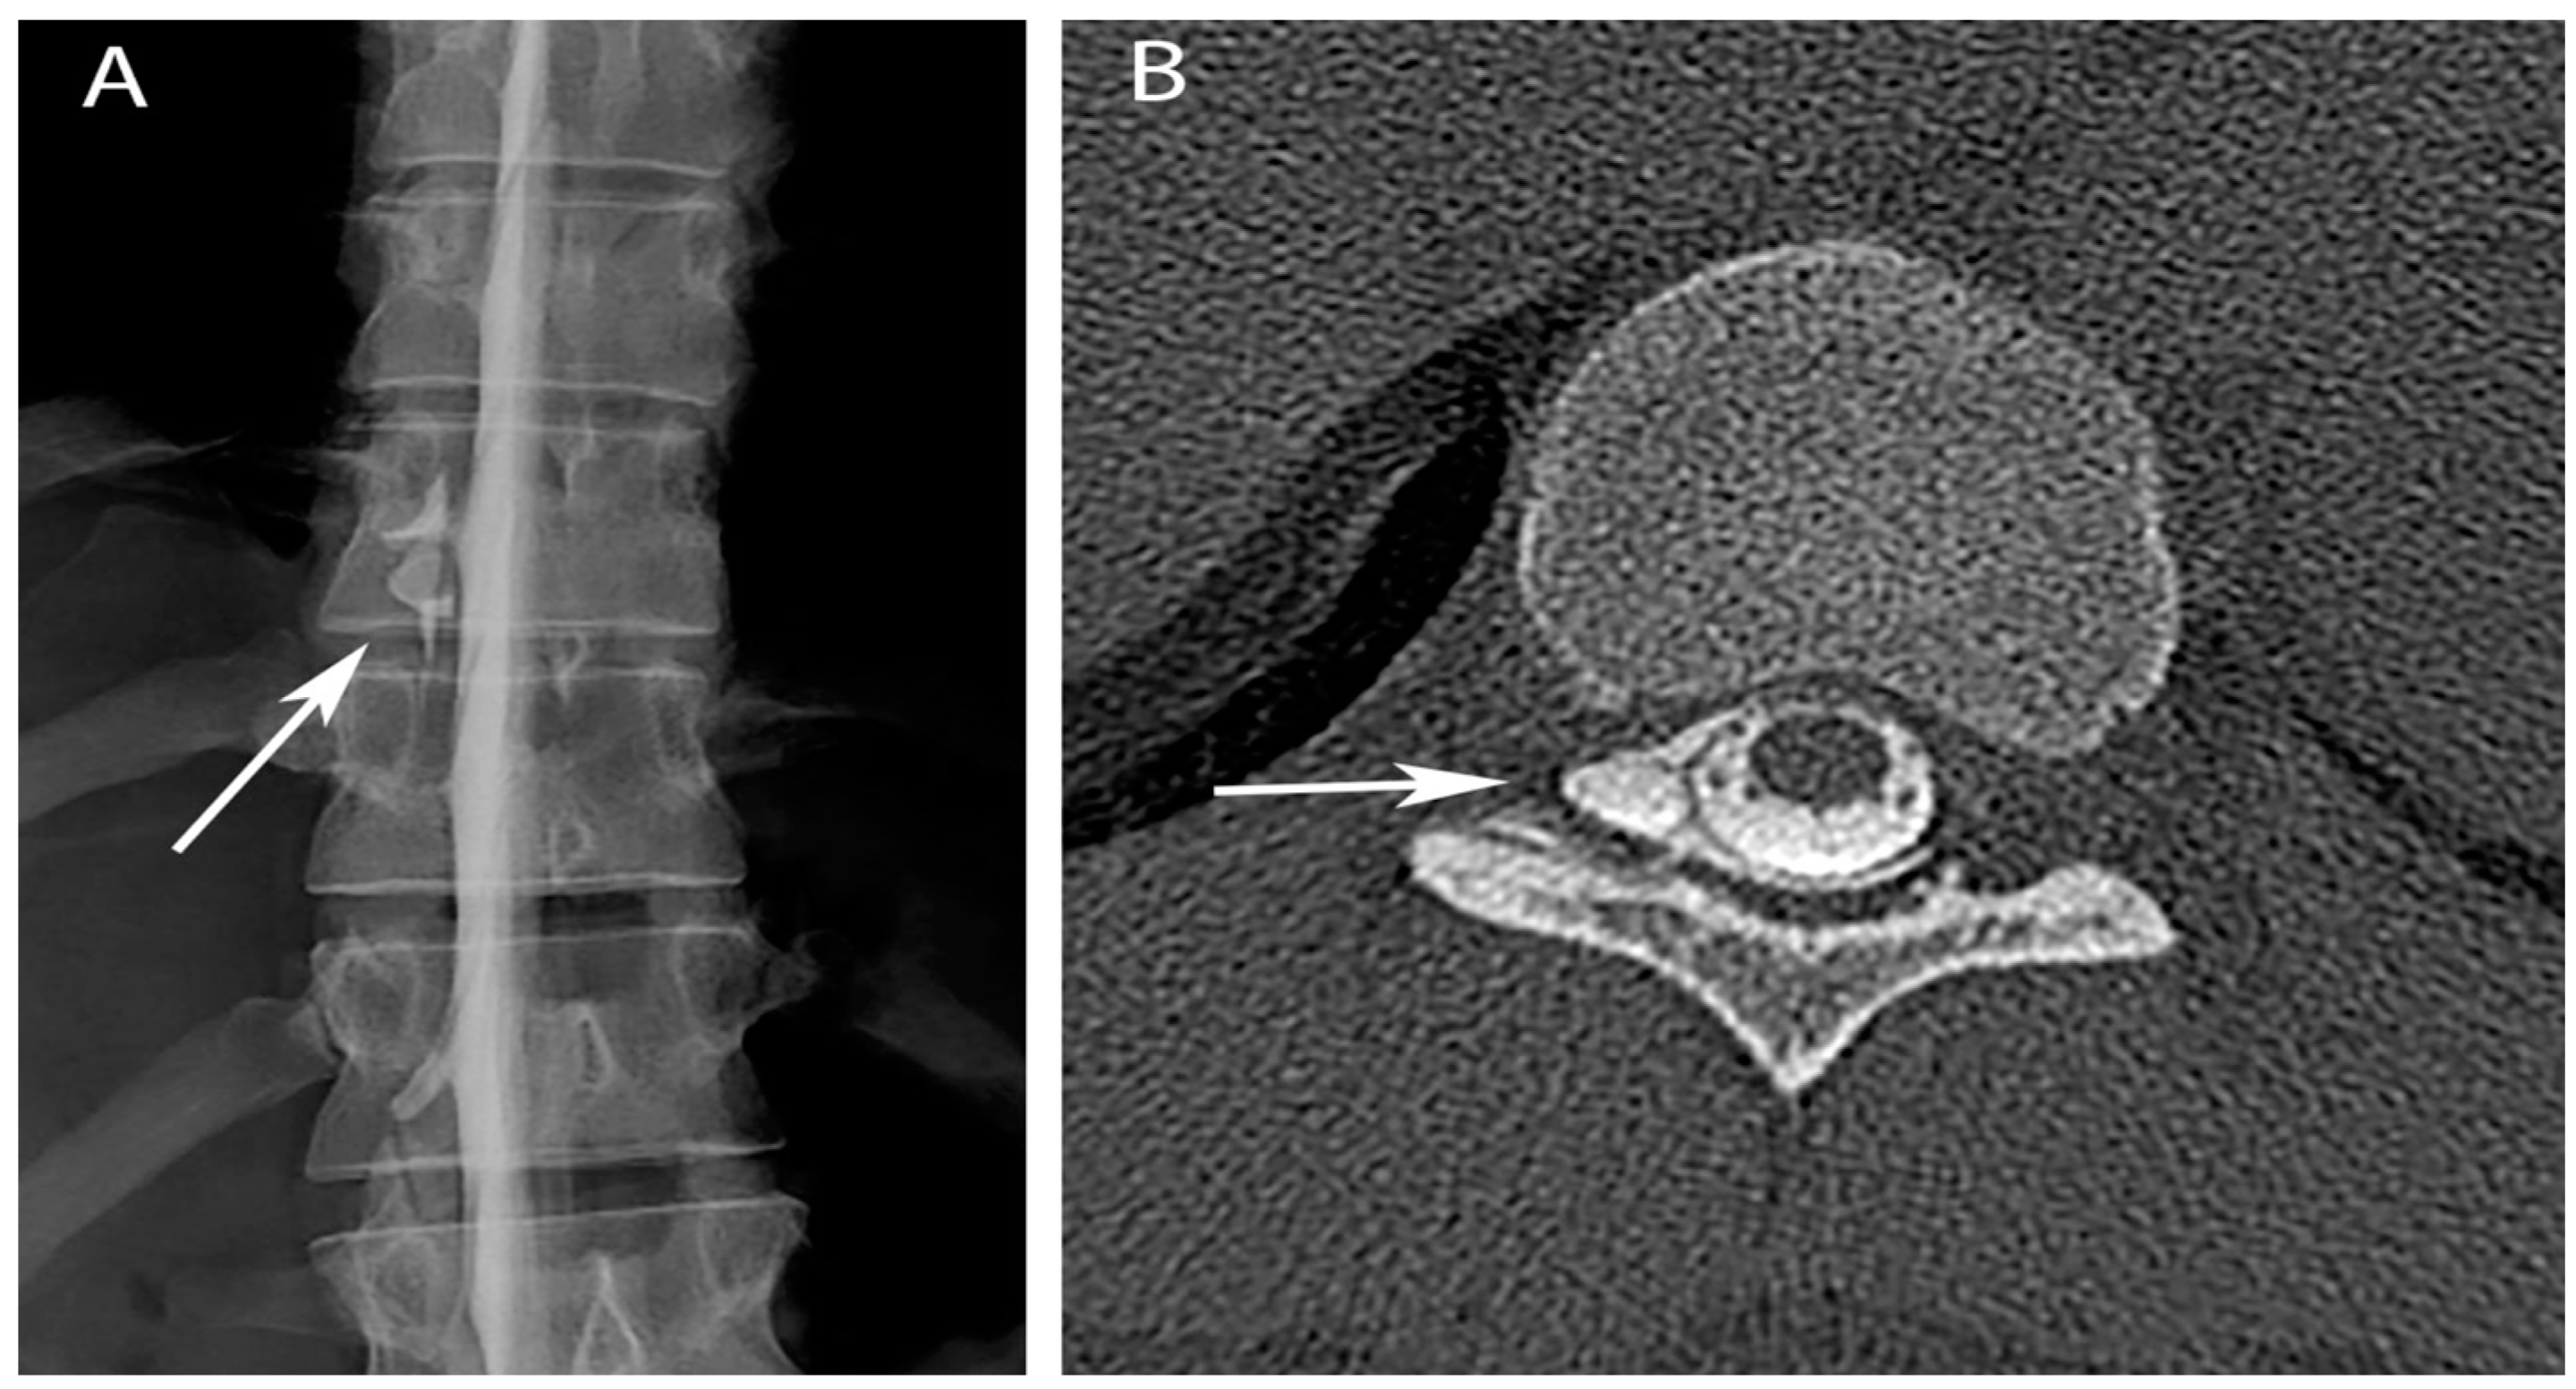

Upon reviewing the MRI findings with the patient, he confirmed that the headache had always been alleviated by lying supine. A CT guided epidural blood patch was performed at L1/L2, and resulted in only modest improvement in headache pain. A second epidural blood patch was performed at T12/L1, again without significant clinical improvement. Repeat MRI of the brain and spine showed progression of spinal cord signal abnormality from T9 to T10. A CT myelogram showed an epidural fluid collection along the right lateral thecal sac extending from T5 to T12, most prominent at T10 (Figure 2A). CT-guided epidural blood patch directed at T9/T10 resulted in only ephemeral relief. A repeat CT myelogram was performed and a targeted interlaminar epidural blood patch was placed at T9/T10 combined with a right transforaminal blood patch at T10/11. This, the fourth epidural blood patch, also only transiently alleviated the patient’s symptoms. The patient was subsequently evaluated for possible surgical repair of the dural tear. Upon the recommendation of neurosurgery, a myelogram with rapid sequence imaging was performed under biplanar fluoroscopy. This study showed CSF egress from the right T10 nerve root sleeve in the right T10-11 foramen extending into the ventral epidural space (Figure 2B). Repeat combined interlaminar and transforaminal epidural blood patch ultimately resulted in resolution of the patient’s headache.

Figure 2. Myelogram (A) and post-myelogram CT (B) show extravasation of contrast (arrows) at the T10-11 neural foramen (right sided extravasation due to patient positioning).